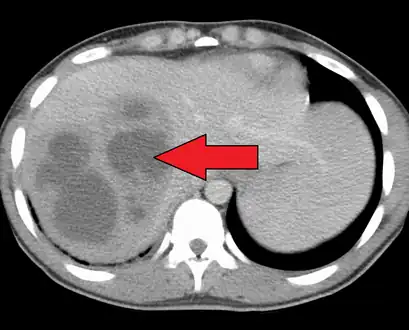

a) Fluoroscopic view shows contrast in collapsed liver abscess red arrow b) fluoroscopic view shows contrast tracking from the liver abscess red arrow -

A large pyogenic liver abscess presumed to be the result of appendicitis